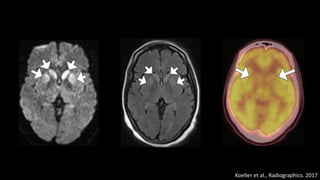

Creutzfeldt-Jakob

• 0,25 a 2 casos/milhão

• Tríade

• Demência rapidamente progressiva

• Mioclonia

• EEC com padrão periódico de onda aguda seguida por onda lenta (complexos

ponta-onda) em frequência aproximada de 1/seg

• Sobrevida média inferior a 1 ano após início dos sintomas.

Koeller et al., Radiographics. 2017

Encefalopatias Espongiformes Transmissíveis

Doenças Priônicas

• Perda neuronal rapidamente progressiva com degeneração

espongiforme, gliose, perda sináptica e ausência de resposta

inflamatória.

• Acentuada atrofia difusa do parênquima cerebral e cerebelar.